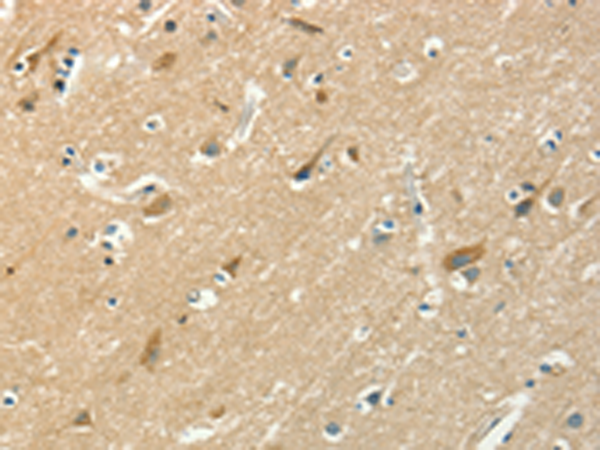

分类: 科研抗体货号: P08025别名: SK 2; SK-2; SPK 2; SPK-2应用: WB,IHC反应种属: Human, Mouse